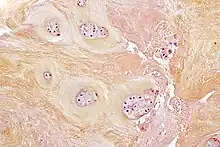

Les disques intervertébraux sont constitués d'un anneau fibreux externe, l'annulus fibrosus, qui entoure une substance gélatineuse interne, le nucleus pulposus[1].

- L'anneau de cartilage fibreux (en latin : annulus fibrosus) se compose de plusieurs couches (lames) de fibrocartilage constitué de collagène de type I et de type II. Le type I est concentré à l'extérieur de l'anneau conférant une grande solidité.

- Il provient embryologiquement du sclérotome, dérivé des somites.

- Le noyau gélatineux ou noyau pulpeux (en latin : nucleus pulposus) permet lui de distribuer uniformément la pression sur tout le disque et empêche le développement de contraintes qui pourraient endommager les deux vertèbres sous et sus-jacente. Le nucleus pulposus contient des fibres en suspension dans un gel de mucoprotéine. Le noyau du disque agit donc comme l'absorbeur des chocs engendrés par l'activité physique de l'organisme et empêche les impacts entre les vertèbres.

- Il s'agit d'un vestige embryologique de la notochorde[2].

- Le noyau pulpeux (ou gélatineux) se compose de grandes vacuoles de cellules d'origine notochordale, de petites chondrocytes, de fibre de collagène, et de protéoglycanes pouvant s'agréger en se liant à l'acide hyaluronique. Cette liaison forme des glycosaminoglycanes (GAG) pouvant être des sulfates de chondroïtine ou des sulfates de kératane[4]. Ces GAG dit "sulfatés" sont chargés négativement et ont la capacité de retenir l'eau dans les tissus. La quantité de glycosaminoglycanes (et donc d'eau indirectement) dans le noyau gélatineux diminue avec l'âge favorisant les phénomènes de dégénérescence[5].